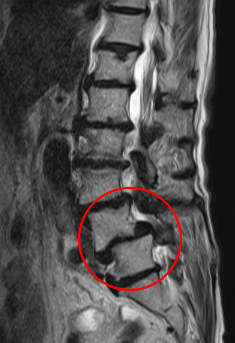

治療前

┃検査・診断

腰椎MRIの画像を確認したところ、L5とL4の腰椎がずれてしまっており、L4/5の脊柱管が圧迫されていました。そのため、痛みと痺れの原因は、すべり症に伴う脊柱管狭窄症と診断しました。